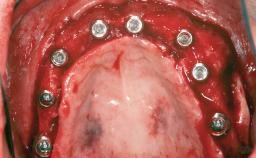

A 47-year-old Caucasian woman with a single-tooth edentulous space at the site of the left maxillary canine was referred for treatment. She had undergone traumatic extraction of this impacted canine several months before referral. Her chief complaint was the dissatisfying appearance of her smile. The patient desired a stable and esthetic rehabilitation of the site. Her dental history showed no evidence of periodontal disease or bruxism. She had no systemic diseases, was not taking any medications, and did not smoke. The extraoral examination revealed a high lip line and an inadequate soft-tissue volume at the defective canine site. Large black triangles were visible between the canine and its adjacent teeth.

Bone Augmentation Staged|Vertical

Augmentation Materials Autogenous chips|Membrane